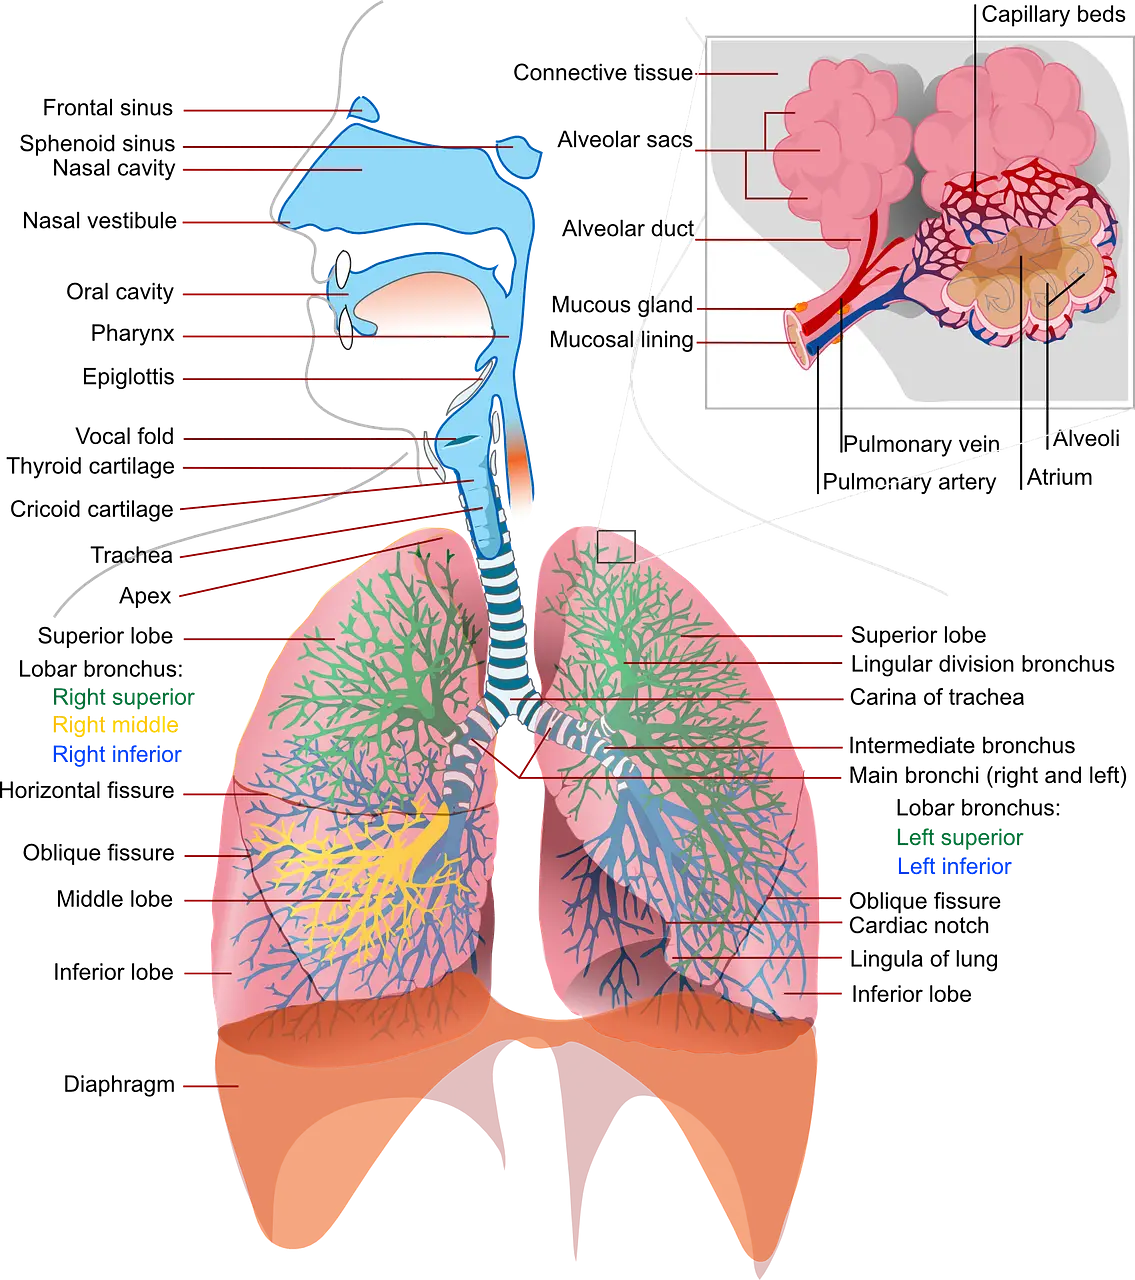

In Traditional Chinese Medicine (TCM), Wei Qi translates as defensive Qi or the immune system. The lungs and Wei Qi are both said to control the body’s surface. The diffusing function of the lungs assists the spread of Wei Qi. But while the lungs may help to spread it, the true genesis of Wei Qi lies in the middle burner.

The lungs are responsible for the skin and the process of breathing. When the lungs’ energy is balanced, Wei Qi is strong, and the immune system can fight any external pathogens. When the lungs’ energy is out of balance, the body is more open to the attack of pathogens such as bacteria and viruses. Symptoms of unbalanced lungs energy, therefore weak Wei Qi include fever, chills, headaches, sore throat, runny nose, coughing.

In TCM, the body is seen as a microsystem where each organ has its function and role, such as:

- The lungs are the storehouse of fluid for the body;

When a pathogen enters the body, the body temperature increases, Wei Qi is Yang (warm, energetic) in nature. Defensive Qi works mainly around the skin and muscles and includes fever, chills, and shivering responses. The stronger one’s immune system, the higher the fever and the worse symptoms. The defence mechanism helps the body into homeostasis. Sweating during a fever is seen in TCM as the body’s way of expelling the pathogen, with the pores letting the pathogen out. It is why TCM doctors will encourage a fever rather than suppress it. When the Wei Qi is weak, the pores and bodies are more open to an attack from the pathogens. So how do we strengthen Wei Qi so that we can withstand a pathogenic attack?